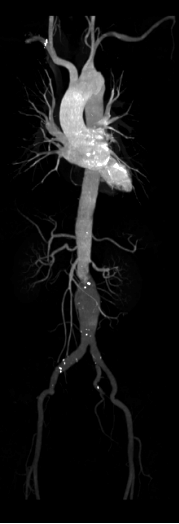

Công nghệ DE tiên tiến: Tích hợp đa dạng kỹ thuật năng lượng kép, hình ảnh rõ nét

Phân tích toàn diện: Cung cấp đồng thời đánh giá định tính và định lượng chuyên sâu.

Giá trị lâm sàng vượt trội: Hỗ trợ nâng cao độ tin cậy trong chẩn đoán và điều trị.

Hình ảnh lâm sàng